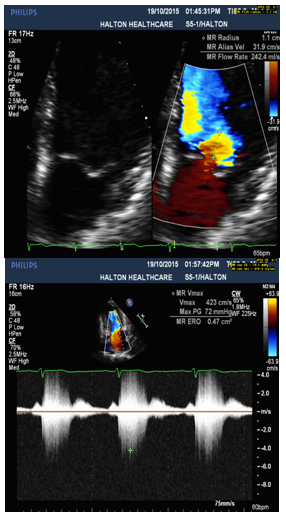

4. Thickened MV leaflets with partial flail of P2 segment of posterior leaflet, and torn chordae (Figure 1).

5. Eccentric anteriorly directed severe MR jet area over 50% (Figure 2) with MR ERO 0.47cm2 (Figure 3) and Vena Contracta 0.76cm (Figure 4), which is consistent with posterior flail leaflet of MVP.

Figure 1: Severe MVP with Partial Flail Posterior Leaflet presented by parasternal LAX view with TTE (Left) and sagittal view at 91○ with TEE (P2 segment) (Right).

Figure 2: Eccentric wall impinging Jet Area over 50% is anteriorly directed, consistent with flail posterior MV leaflet.

Figure 3: PISA: large flow convergence radius 1.1cm(Left) with MR ERO 0.47 cm2 and dense, early peaking and triangular CW Doppler MR jet(Right).

Diagnosis of MVP with flail posterior leaflet and grading of MR severity

Physical examination and 2-dimensional (2D) echocardiography are the diagnostic gold standards for MVP [4]. According to echo findings I listed above, together with the patient’s symptoms (SOB and chest discomfort) and pansystolic murmur heard at the apex, the patient was diagnosed as severe MVP with flail posterior leaflet. Echo criteria of flail leaflet includes leaflet tip pointing to LA without systolic coaptation (Figure 1,2,4), torn chordae, double contour (parallel sign) between flail and normal leaflets (Figure 4), and eccentric MR jet direction opposite to the location of the flail leaflet (Figure 2 and 4) [3,4]. Doppler echocardiography is essential in determining the severity of MR. According to ASE guideline, criteria for severe MR includes a vena contracta width ≥ 0.7 cm, large central mitral regurgitation jet (area >40% of left atrium), pulmonary vein reversal, effective regurgitant orifice >40 mm2 and others [3,5]. The echo findings and Doppler measurements strongly support a severe MR in the patient (Table 1).